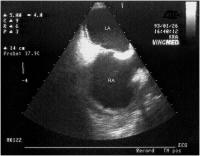

Vena cava sup. - Subtotale Thrombose

Abbildung 3a-b